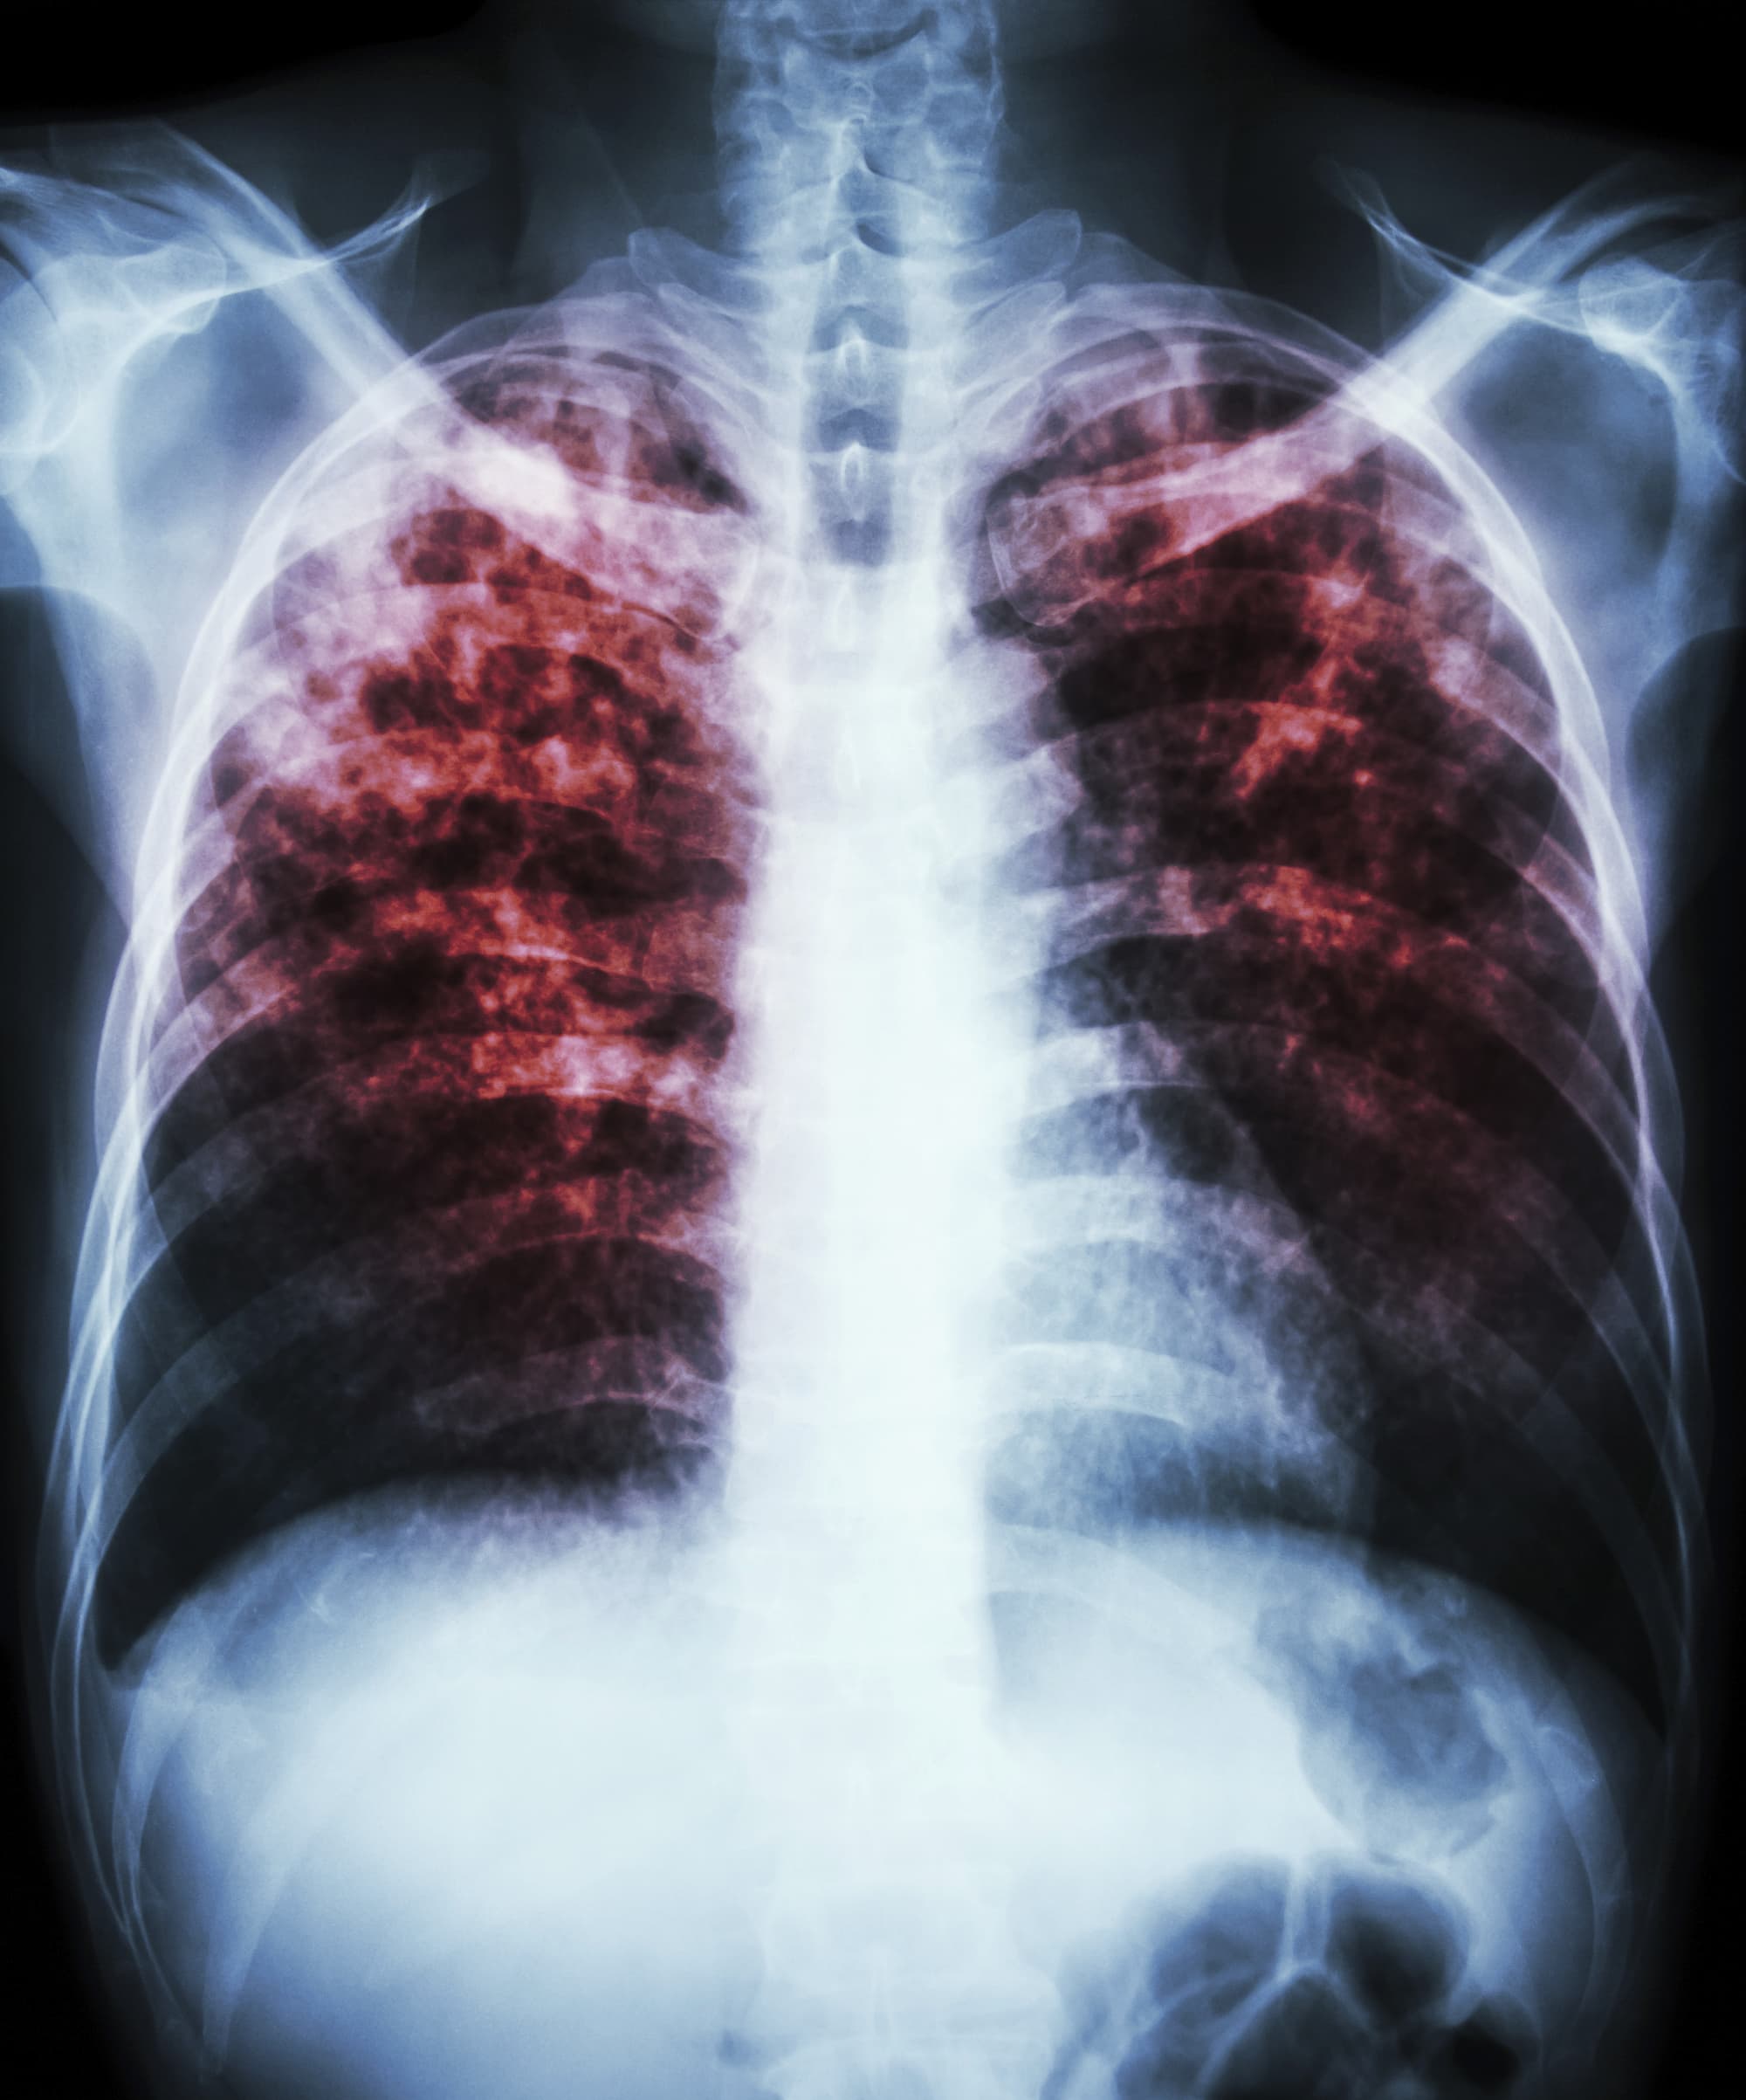

Die Tuberkulose ist eine meldepflichtige Erkrankung. Bevor Flüchtlinge in einer Gemeinschaftsunterkunft untergebracht werden können, müssen laut dem Infektionsschutzgesetz ansteckende Krankheiten ausgeschlossen werden. Eine aktive, ansteckende Tuberkulose kann mit Hilfe einer Röntgenaufnahme der Lunge entdeckt werden. Und so schleust beispielsweise das Gesundheitsamt Hamburg-Mitte tagtäglich 100 bis 200 über 15-jährige Flüchtlinge durch ihre Röntgenabteilung. "Wenn etwas auffällig ist, versuchen die dortigen Ärztinnen, die Betroffenen in einem Krankenhaus unterzubringen und mit weiteren Untersuchungen eine Tuberkulose zu bestätigen oder auszuschließen", erklärt Roland Diel. Dabei wird zum Beispiel geprüft, ob im Hustenauswurf Tuberkelbakterien zu finden sind.